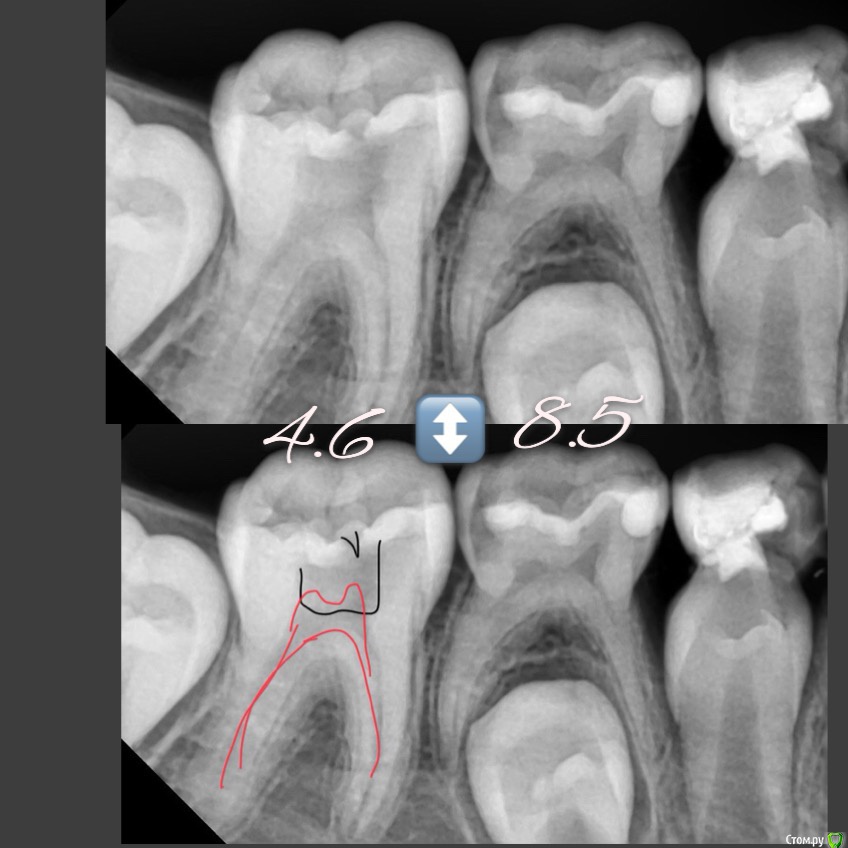

CRAZYDUCK Опубликовано 7 мая, 2018 Автор Поделиться Опубликовано 7 мая, 2018 (изменено) Лечение пульпита ; 6.4 необратимый , 6.5 обратимый .Продолжительность 1:15 час ( с момента входа в кабинет и до прощания )6.4-каналы -протейпер дентсплай Sx, ручные инструменты 25.02, гипохлорит 3,2%, пломбирование каналов Йодотин( отличный аналог метапекса , который всегда идёт из канюли в отличии от метапекса ), восстановление культи СИЦ, коронка 3М ESPE стальная .6.5 - ампутация , ХГ2%, спонтанный гемостаз , рутдент быстротвердеющий ( МТА), изоляция Calcimol, реставрация Charisma. Все лечение в одно посещение - долго для ребёнка 4 лет , но так лучше . Пришла к такому методу работы относительно недавно .Больше нравится работать таким образом - 2-3 рядом стоящих зуба в одно посещение . В этот раз было уже не до фото . Для начинающих коллег на rvg выделила полости кариозные и пульпарные полости. Изменено 7 мая, 2018 пользователем CRAZYDUCK 4 Ссылка на комментарий